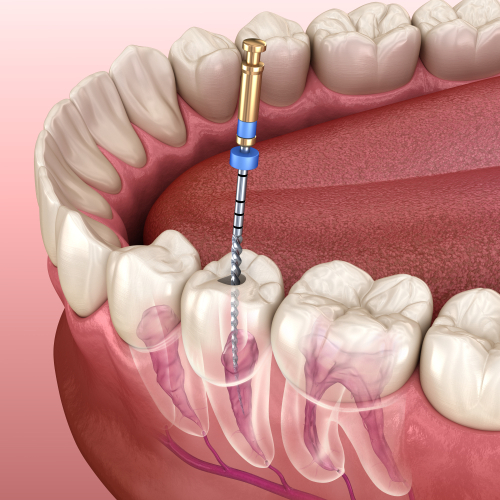

Queen City Family Dentistry, situated at 31 Maple Rd in the welcoming community of Amherst, New York, stands as a pillar of comprehensive oral healthcare for families across the Buffalo metropolitan area. While specific founding details for this particular practice are not extensively documented in public directories, the name 'Queen City' proudly anchors it to the rich heritage of Buffalo, NY, historically known as the Queen City. The practice embodies a modern, patient-centric approach to dentistry, built upon a foundation of trust, clinical excellence, and a genuine commitment to creating a comfortable, anxiety-free environment for patients of all ages. The mission of Queen City Family Dentistry is straightforward yet profound: to provide exceptional, personalized dental care that promotes lifelong oral health and radiant smiles. This mission is driven by the understanding that dental health is intrinsically linked to overall well-being, confidence, and quality of life. The practice is believed to be led by dedicated dental professionals who prioritize continuing education, ensuring they remain at the forefront of dental technology and techniques. This commitment allows them to offer a blend of time-tested procedures and cutting-edge treatments. What truly sets Queen City Family Dentistry apart is its holistic 'family-first' philosophy. The practice is designed to be a one-stop dental home where children can have their first dental visits, adults can receive routine and complex restorative care, and seniors can maintain their oral health with dignity. This eliminates the need for families to coordinate care across multiple specialized offices, fostering consistency and a deep, trusting relationship between the dental team and the family unit. The practice’s environment is meticulously crafted to dispel the common anxieties associated with dental visits. From a calming and welcoming reception area to treatment rooms equipped with patient comforts, every detail is considered. The team is renowned for its compassionate communication, taking ample time to explain procedures, discuss options, and listen to patient concerns without ever rushing. This empathetic approach, combined with clinical expertise, forms the core of their unique value proposition. They don't just treat teeth; they care for people. Expertise at Queen City Family Dentistry spans the full spectrum of general, preventive, cosmetic, and restorative dentistry. The practitioners are skilled in managing the unique dental needs of each life stage, applying a gentle touch with pediatric patients, a meticulous eye for detail in cosmetic cases, and a pragmatic, pain-management-focused approach for complex adult restorations like crowns, bridges, and dental implants. Their preventative programs are robust, emphasizing education and early intervention to help patients avoid more serious issues down the line. In the competitive landscape of dental practices in Amherst, Queen City Family Dentistry distinguishes itself through its unwavering focus on creating a positive, educational, and stress-free patient experience. They leverage advanced digital technology—such as digital X-rays for reduced radiation and intraoral cameras for patient education—not as a novelty, but as tools to enhance accuracy, efficiency, and patient understanding. The practice operates with transparency regarding treatment plans and financial options, believing an informed and financially comfortable patient is a partner in their own care. Ultimately, Queen City Family Dentistry is more than a healthcare provider; it is a community partner invested in the smiles and health of Amherst and its surrounding neighborhoods. Their commitment to excellence, personalized care, and a warm, family-friendly atmosphere ensures that every visit contributes to building a foundation of optimal oral health that lasts a lifetime.